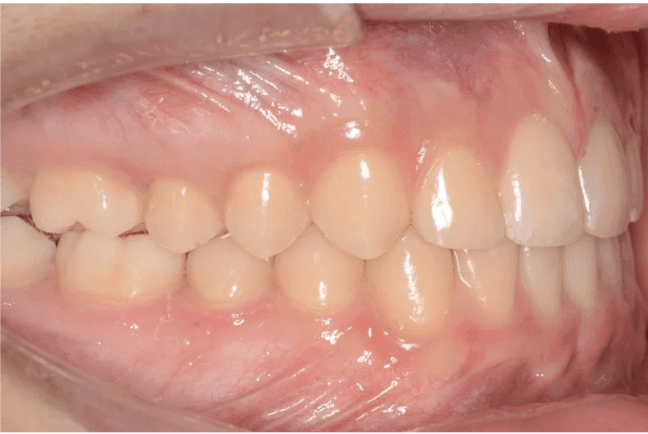

Final results

INTRAORAL